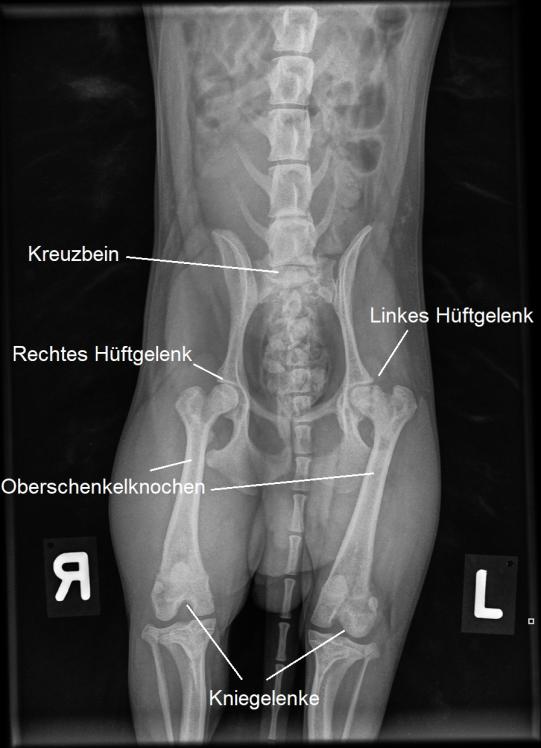

Im Untersuch scheint die Hüftregion des Junghundes schmerzhaft. Die Ursache dafür ist in einem Röntgenbild klar ersichtlich: Der linke Oberschenkelkopf escheint stark verändert; er ist nicht wie sein rechtes Gegenstück schön rund, sondern etwas eckig und von verminderter Röntgendichte. Mero leidet an einer sogenannten Aseptischen Femurkopfnekrose (Morbus Legg-Calvé-Perthes).